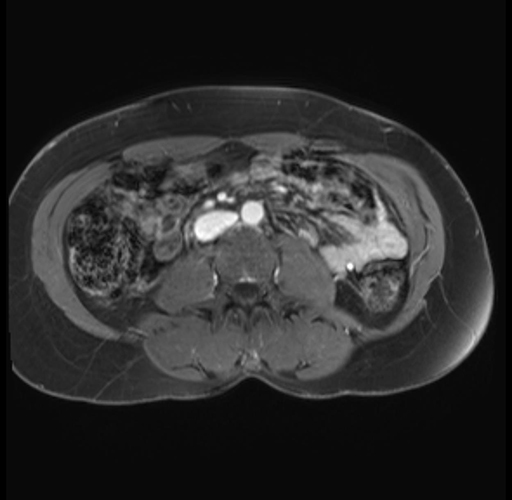

Imaging Analysis

Look through the patient's CT scan to identify any areas of concern for the necessary procedure.

Based on your CT findings, which issue(s) are present and would give reason for "planned slowing down moment(s)" in this case?